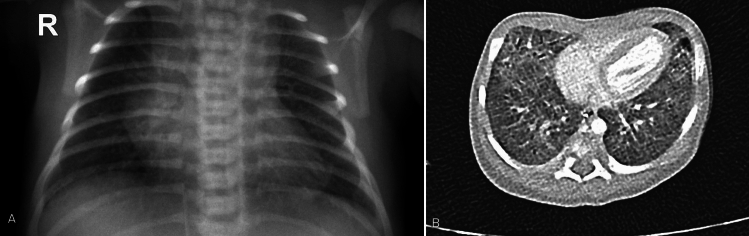

Results: We reported three off-label cardiorespiratory reasons to use IL-1Ra from our series: (i) chronic lung disease with pulmonary hypertension, (ii) interstitial lung disease with pulmonary hypertension to facilitate the weaning from respiratory support, and (iii) post-surgical polyserositis if effusions accumulate despite drainage. In all our patients, the drug was administered at a dosage of 10 mg/kg/day. The route of administration was chosen based on the patient's clinical characteristics, with the subcutaneous and intravenous routes being comparable in efficacy. The duration of therapy was modulated based on the patient's clinical response, with a minimum duration of 4 months. A total of 308 retrieved articles were screened, and then full texts of records deemed eligible for inclusion were assessed. Based on the literature search and our five cases, a total of 17 infants were treated with anakinra outside its approved indications. The major off-label use was for hemophagocytic lymphohistiocytosis/macrophage activation syndrome, followed by multisystem inflammatory syndrome in children and Kawasaki disease, as in two of our cases.

背景:Anakinra是一种白细胞介素-1受体拮抗剂(IL-1Ra)。由于IL-1已被证明在不同自身炎症性疾病的病因学中发挥关键作用,阻断其通路已成为一个重要的治疗靶点,即使在新生儿中也是如此。目的:我们的目的是报告我们使用阿那白那治疗特定新生儿炎症的经验。方法:我们描述了自2020年起在意大利罗马Bambino Gesù儿童医院IRCCS新生儿重症监护病房(NICU)收治的5例新生儿或3个月以下婴儿的临床处理。从电子病历中收集新生儿重症监护病房住院的病史和临床资料。此外,我们对截止到2024年4月5日的前3个月的说明书外anakinra进行了文献综述。我们从本综述中排除了冷冻素相关周期性综合征、白细胞介素-1受体拮抗剂缺乏和甲羟戊酸激酶缺乏的病例,阿那白素是已知的治疗方法。结果:我们报告了本系列中使用IL-1Ra的三个非适应症心肺原因:(i)慢性肺部疾病伴肺动脉高压,(ii)间质性肺疾病伴肺动脉高压,以促进脱离呼吸支持,(iii)术后多浆膜炎,如果引流后积液积聚。在我们所有的患者中,给药剂量为10mg /kg/天。根据患者的临床特点选择给药途径,皮下给药途径和静脉给药途径疗效相当。治疗的持续时间根据患者的临床反应进行调整,最小持续时间为4个月。总共筛选了308篇检索到的文章,然后评估被认为符合纳入条件的记录的全文。根据文献检索和我们的5例病例,共有17名婴儿在其批准的适应症之外接受了阿那金那治疗。主要的适应症外使用是用于噬血细胞淋巴组织细胞增多症/巨噬细胞活化综合征,其次是儿童多系统炎症综合征和川崎病,如我们的两个病例。结论:根据我们的病例系列和文献回顾的结果,可以考虑在一线治疗难治性炎症的新生儿中超说明书使用阿那白拉。有必要进行前瞻性的多中心研究,以确定anakinra是否是这些婴儿预防早期炎症性疾病的安全治疗选择,以及在哪些情况下它可以提高临床结果。